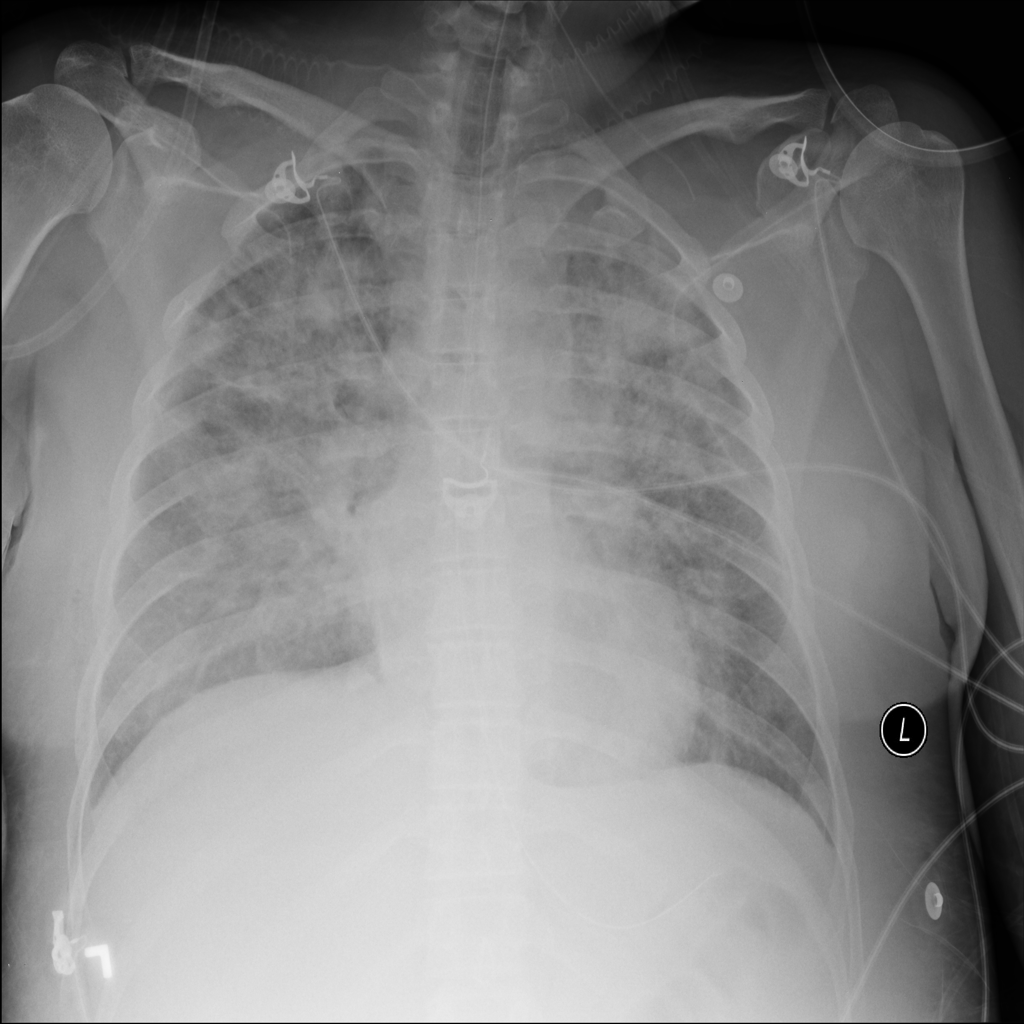

PAT-E828 · IMG-004Edema

PAT-E828 · IMG-004

AP